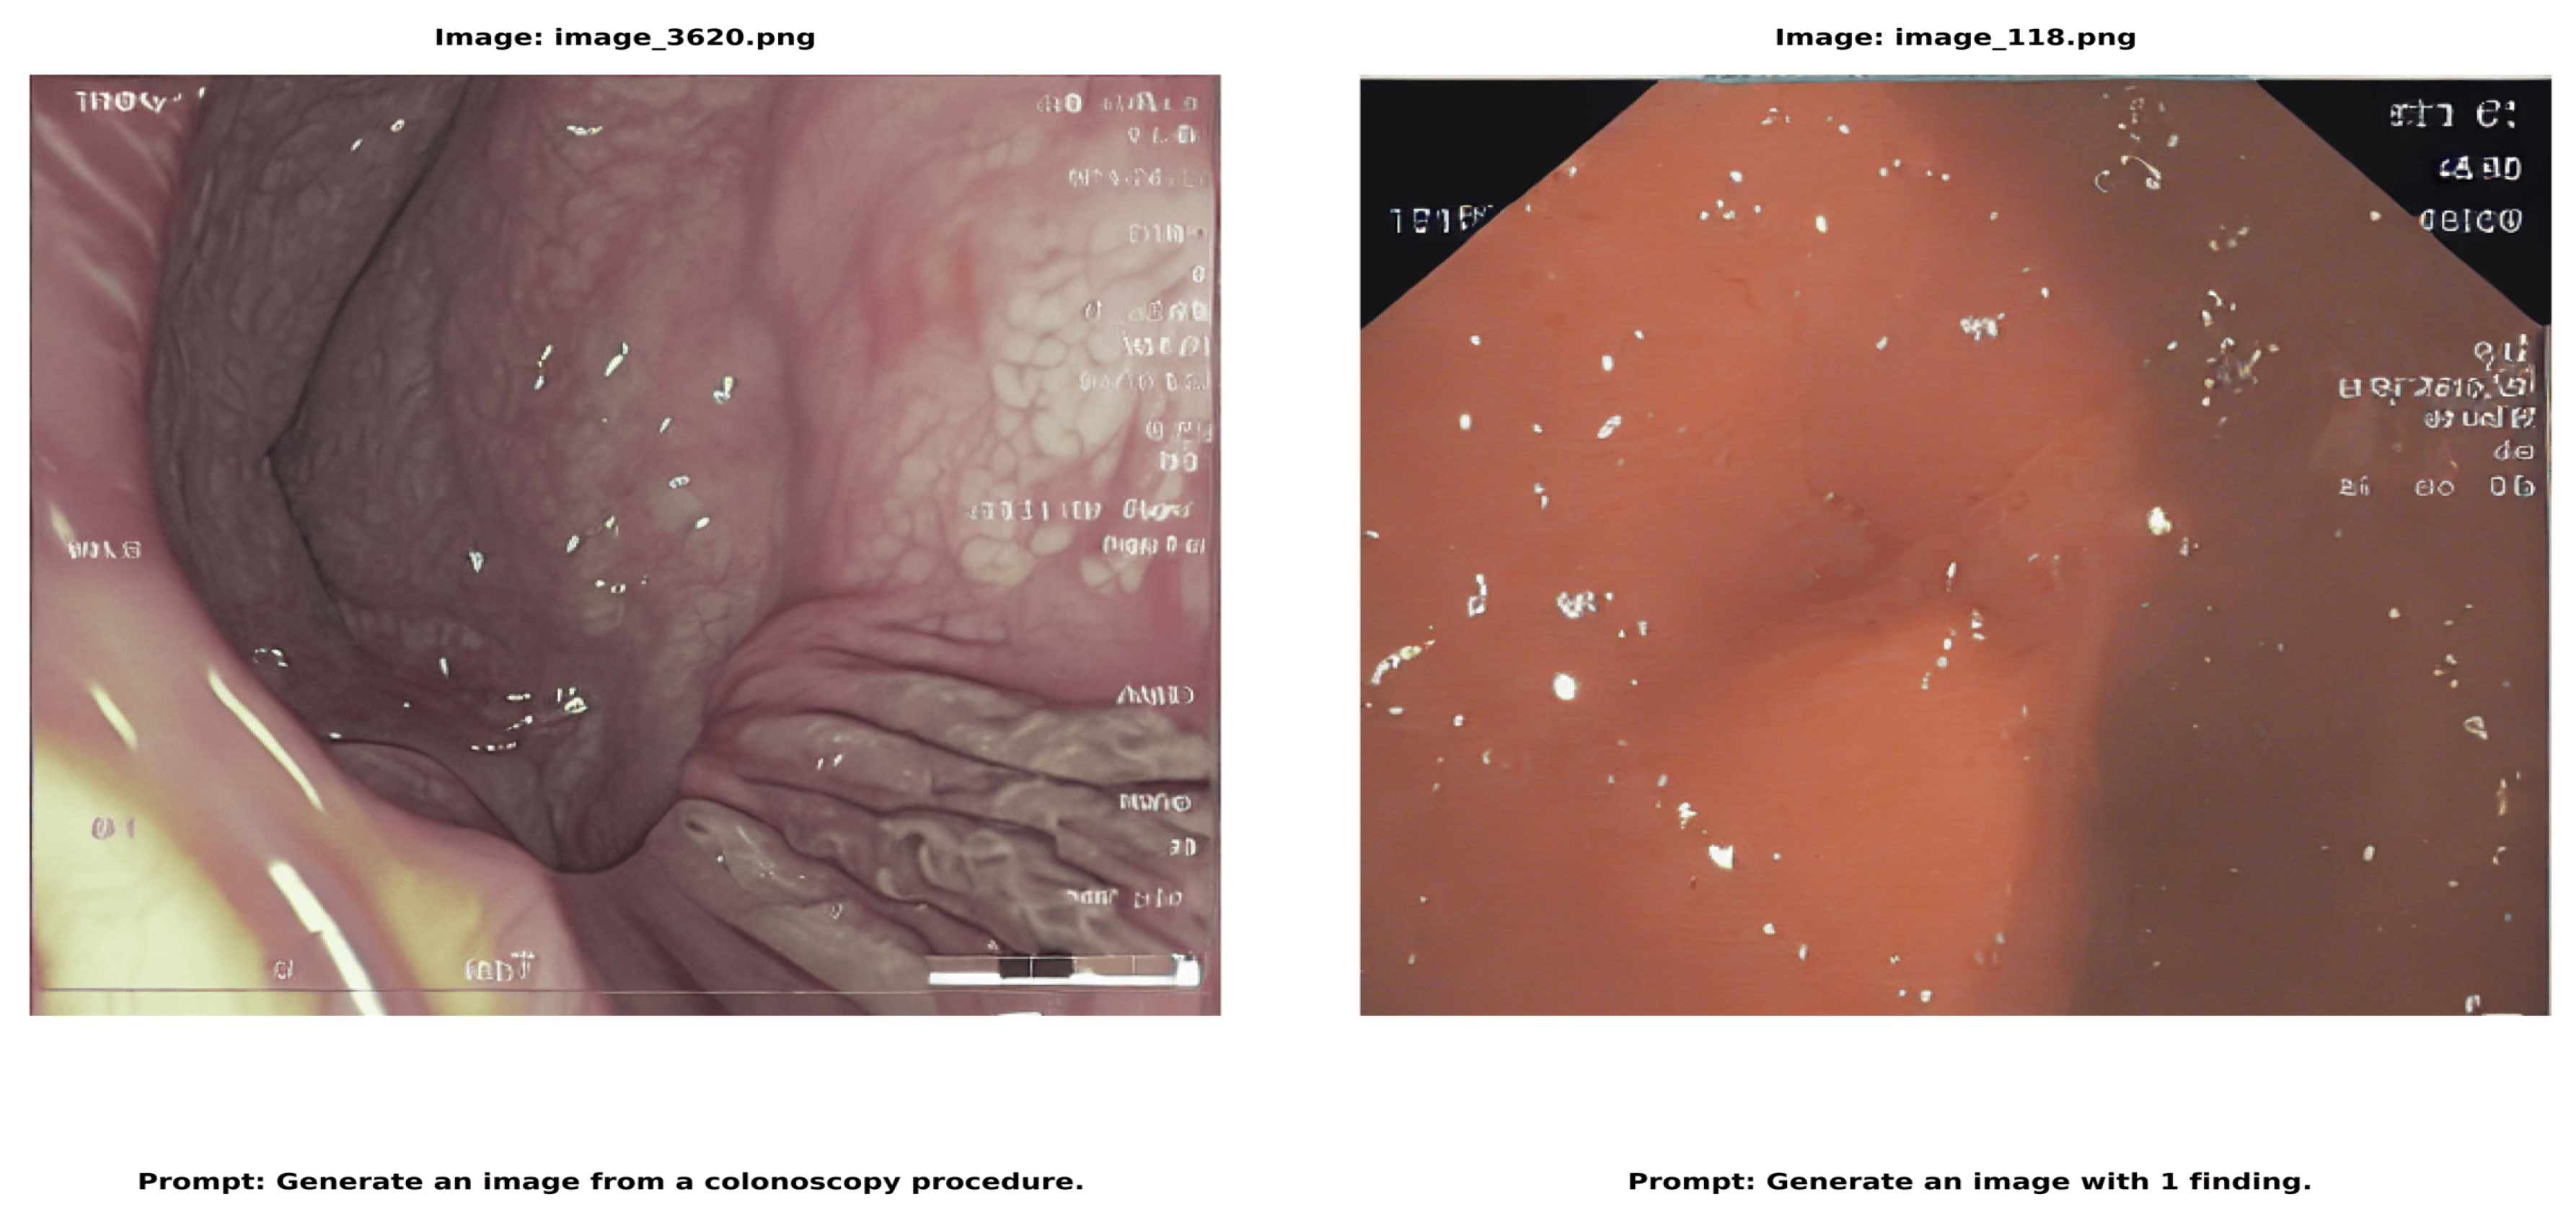

where X and Y represent the predicted and ground truth segmentation masks, respectively, TP denotes true positives, FP denotes false positives, and FN denotes false negatives. Our evaluation approach integrates many metrics to thoroughly evaluate distinct facets of the system’s performance. The quality of images is assessed by the Inception Score (IS) and Fréchet Inception Distance (FID), which offer quantifiable metrics for the caliber of synthetic image synthesis. Classification performance is evaluated using many metrics, such as accuracy, precision, recall (sensitivity), F1 score, and area under the ROC curve (AUC-ROC). For segmentation tasks, we assess quality by Intersection over Union (IoU), Dice coefficient, Peak Signal-to-Noise Ratio (PSNR), and Structural Similarity Index (SSIM), guaranteeing a comprehensive evaluation of segmentation precision and dependability [38,39,40,41,42,43,44]. The CLEF data comprises of text-image pairs as seen in Figure 3.

Figure 3. displays image-text pairs in which a number of descriptive text prompts are paired with each colonoscopy image. In addition to having distinct labels (such as 064086616.png and 040086376.png), each image features a set of text questions that offer several approaches to describing or creating comparable medical situations. This pairing structure produces a comprehensive dataset with detailed descriptions of every medical image from various textual perspectives. The instructions in each image address a variety of topics related to the medical scene, from identifying locations and image features to describing apparent instruments and discoveries. This creates a rich image-text relationship in which a single medical image is connected to multiple relevant text descriptions, each highlighting different aspects of the same clinical scenario.

Figure 3. The dataset shows image-text pairs where each colonoscopy image is matched with multiple descriptive text prompts images